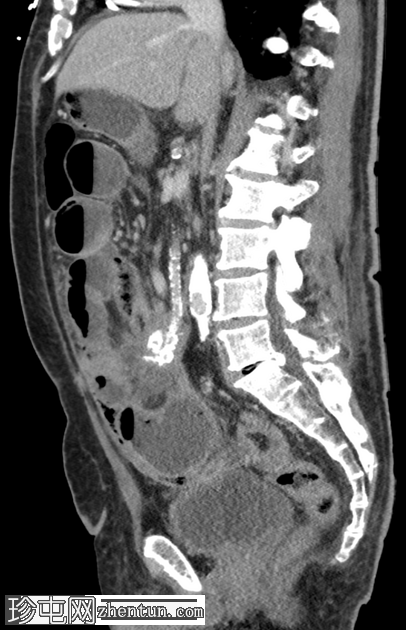

冠状位增强扫描(门静脉期)

肠系膜可见一软组织密度增高的肿块,大小为34 x 67 mm,部分钙化,边缘呈毛刺状,牵拉多个小肠袢,提示存在促纤维增生反应。

肠系膜上动脉(SMA)与该肿块关系密切。

肠系膜充血和肠壁增厚。近端小肠轻度扩张。

根据大小标准,未见腹盆腔淋巴结肿大。

右下腹可见腹膜结节,最大结节大小为28 x 19 mm。

大网膜呈结节状增厚。

少量腹水和胸腔积液。

未见其他转移。

未发现疑似小肠原发肿瘤

显著的动脉粥样硬化、多发性小肾梗死和非梗阻性结石。